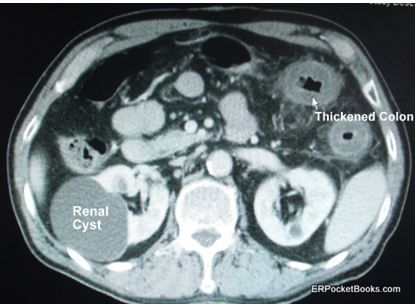

Diagnostic testing includes a complete blood cell count, metabolic panel, liver function tests, lipase test, and a CT scan of the abdomen. Laboratory values are all normal except for a potassium level of 3.1 mEq/L and a white blood cell (WBC) count of 19.2 x103/µL. The CT scan was ordered primarily because of the elevated WBC count and one cut from that scan is shown in the Figure. (Please click on Figure to enlarge)

Answers (See Figure labels; click on Figure to enlarge)

- Incidental findings: renal cysts, one large calcified aorta

- Pathologic finding: thickened colonic wall